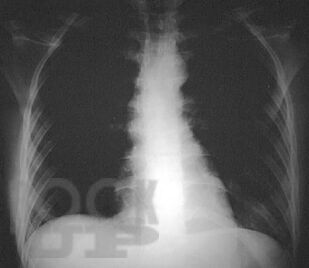

В данном учебном пособии на основе клинических рекомендаций и анализа современной литературы представлены анатомо-физиологические особенности и методы исследования сердечно-сосудистой системы у детей, даны современные представления о наиболее часто встречающихся патологиях сердца и сосудов в детском возрасте. В пособии рассмотрены новейшие подходы к ранней диагностике и терапии врожденных пороков сердца, кардитов и артериальной гипертензии удетей.